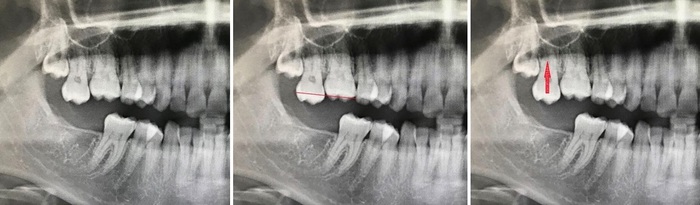

«Свято место пусто не бывает». При длительном отсутствии какого-либо зуба, соседние зубы начинают постепенно смещаться в их сторону. Подобные перемещения происходят только вперед. То есть, если удалить 8ку, то 7ой зуб не наклонится назад подобно тому, что представлен на снимке. Если нет проблем с прикусом. (смыканием зубов).